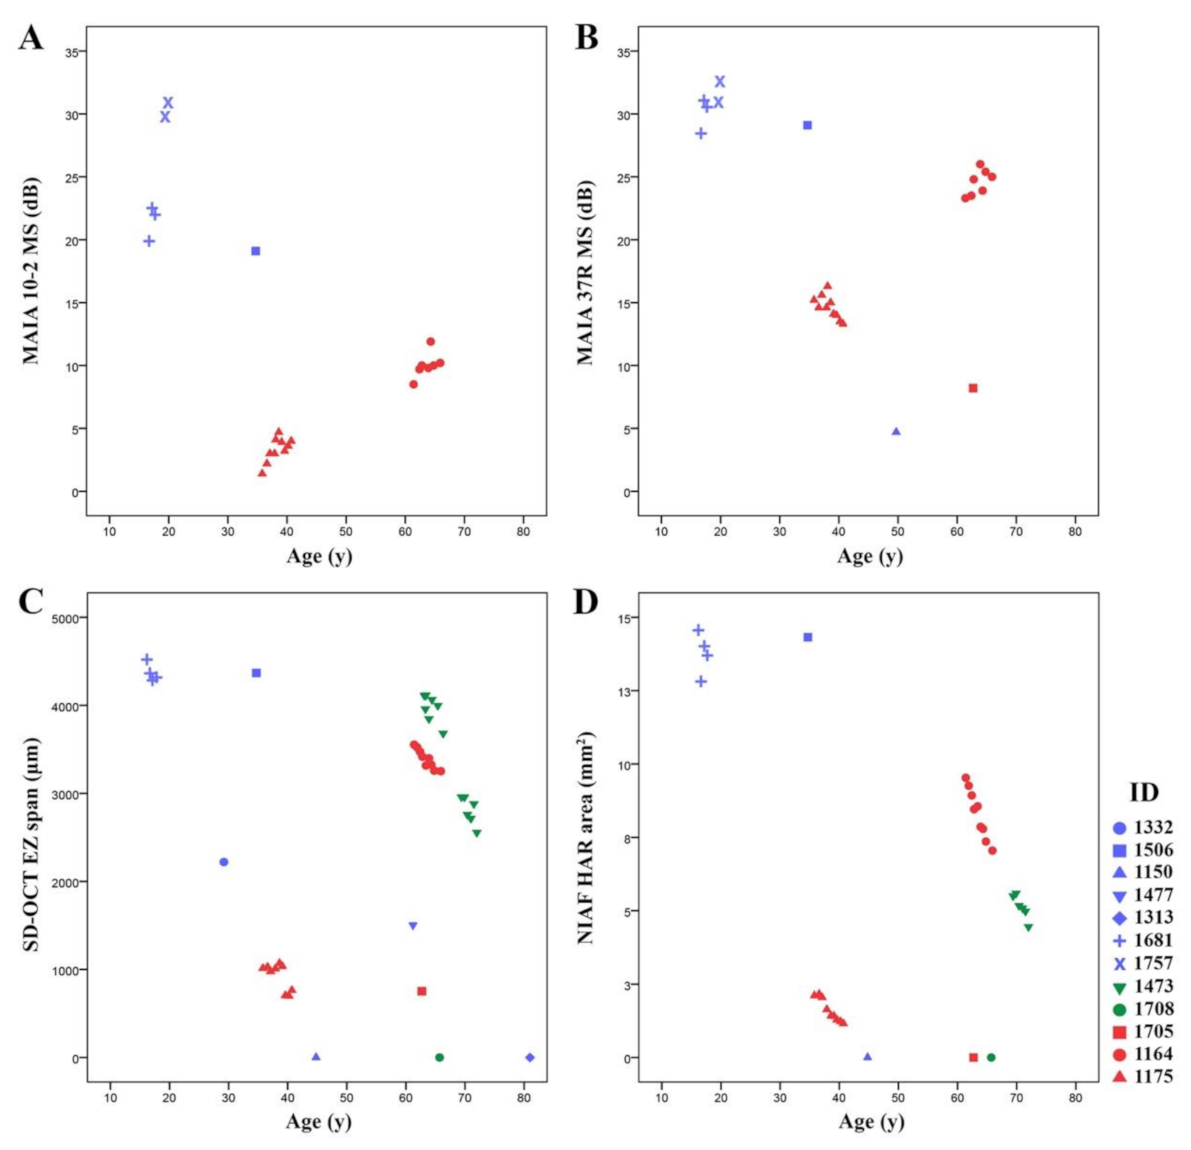

3.3. Natural History of Disease Progression

3.4. Phenotype Patterns

4.2. RP11 Progression May Not Follow a First-Order Exponential Curve